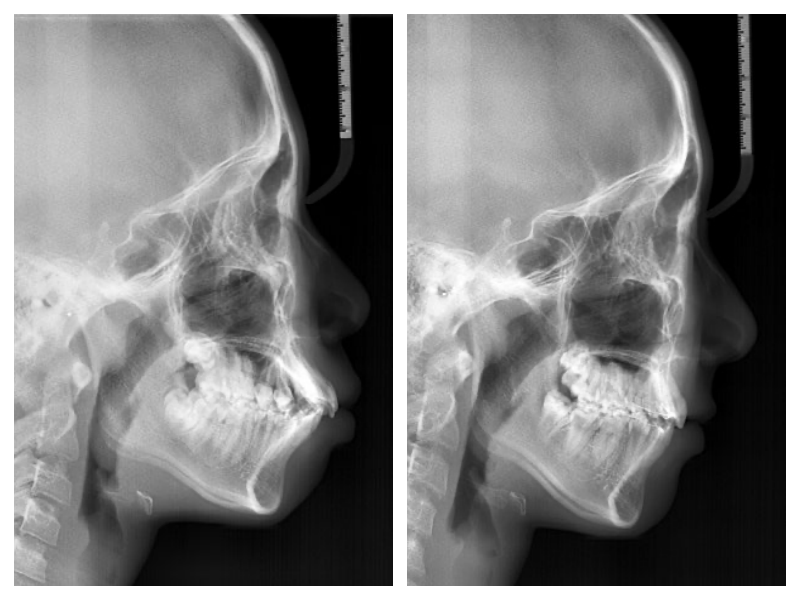

돌출입교정

돌출과 비대칭 교정치료